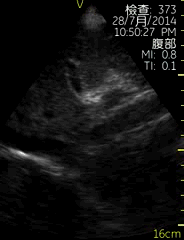

Vscan临床图片 腹部